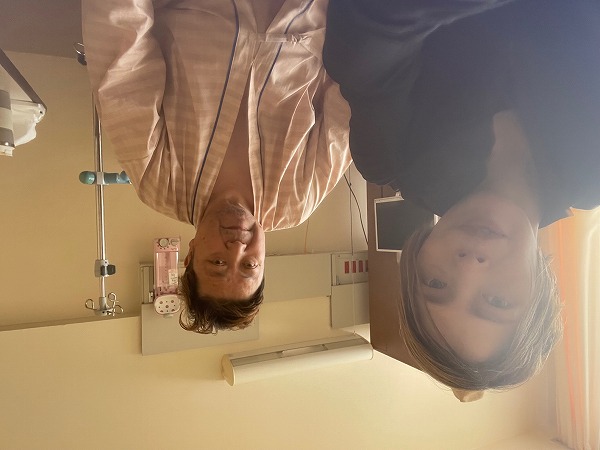

14日、少し起きれるようになったが、まだ全身が痛い。尿管と腎臓に入る管を除いて夕方取れる。鼻、背中の痛み止めの管、両手の点滴用注射器など外れただけでも気分がいい。夕方、眞月美雨さんが寄ってくれた。生きている証に「一緒に写真を!」をと言うのでパチリ~!☆!♡